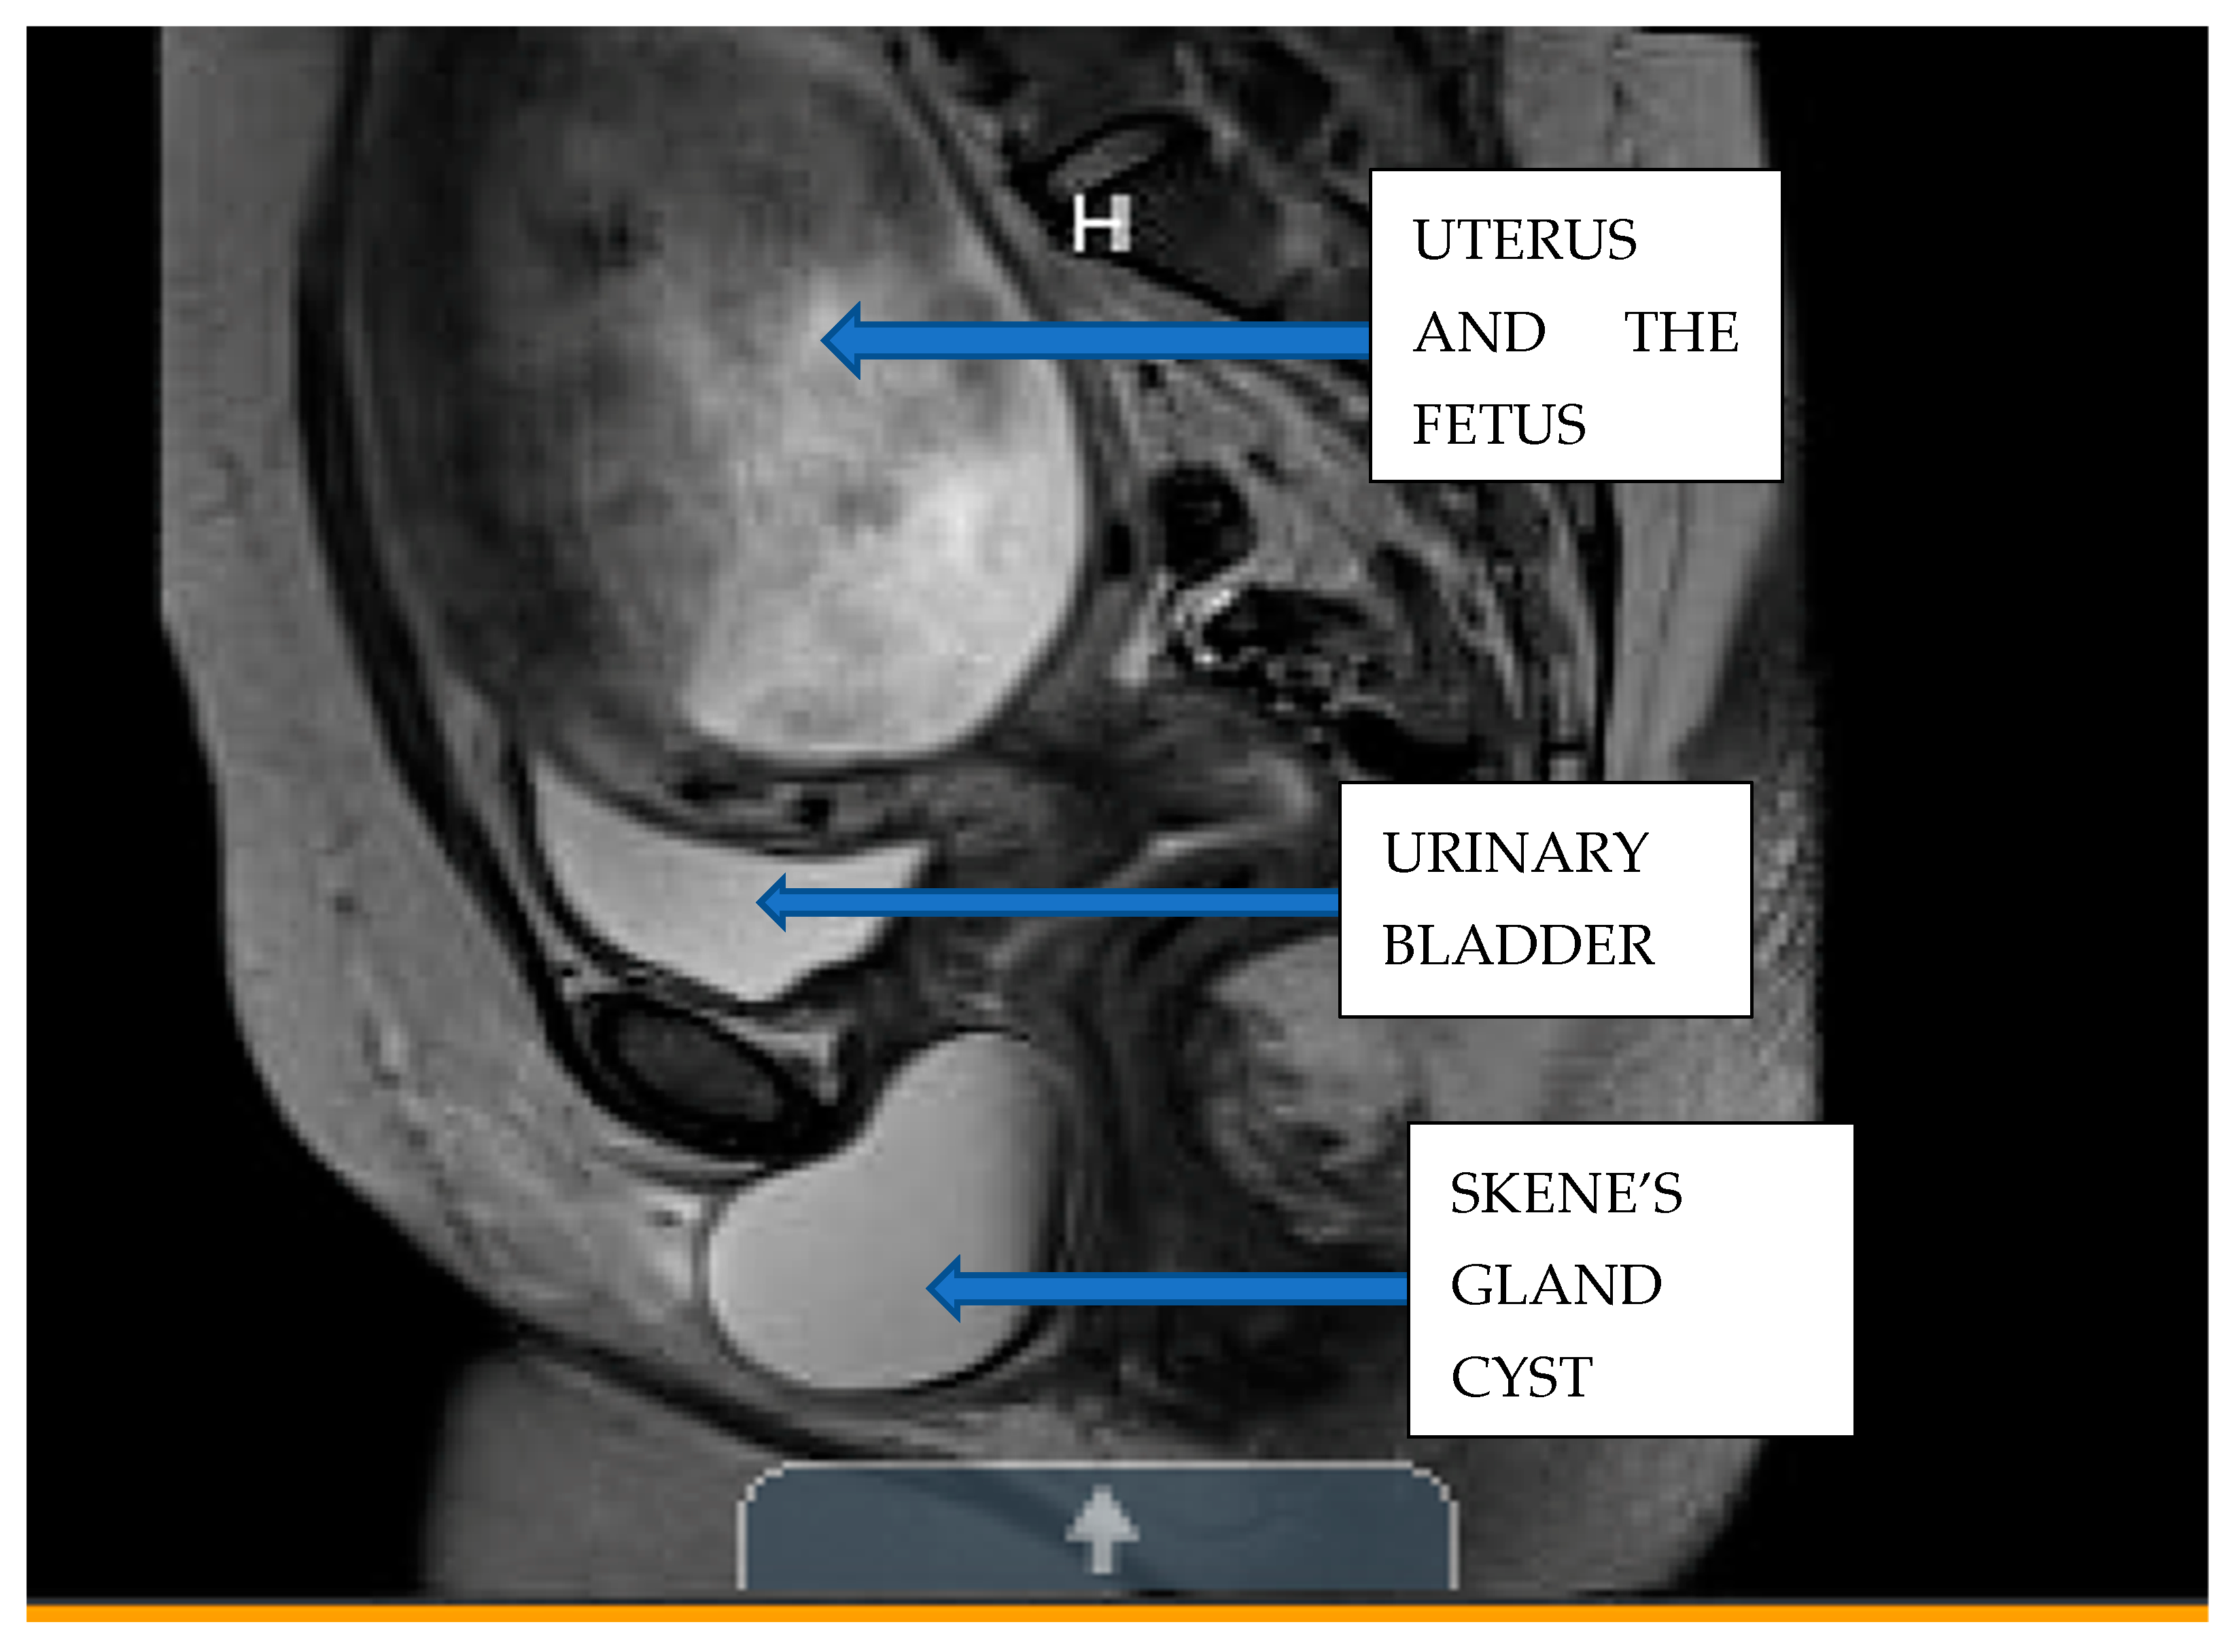

Clinical Findings: The patient’s primary obstetrician and gynecologist performed a pelvic exam and ultrasound, and her physician was concerned because of the large size of the mass, which appeared to be obstructing the vaginal introitus and compressing the external urethral meatus (Figure 2 and Figure 3). The fetal anatomy ultrasound performed did not show any evidence of significant fetal anomalies. She was immediately sent to the emergency department for further evaluation, where a pelvic MRI without contrast was performed to assess the origin of the mass and its extent (Figure 4 and Figure 5).

Diagnostic Assessment: The MRI found a lesion that abuts and indents the posterior wall of the urethra (Figure 2). It did not arise or connect to the urethra. It was a benign-appearing cystic lesion between the posterior wall of the urethra and the anterior wall of the vagina. The cystic lesion measured approximately 9 cm × 7 cm × 6 cm. It appeared to be a cyst with hemorrhagic or proteinaceous debris with a thin, smooth wall (Figure 2). There was no surrounding inflammation or tissue infiltration.

Figure 3. Sagittal view of the MRI image without contrast of maternal pelvis showing the Skene’s gland posterior to the urethra.